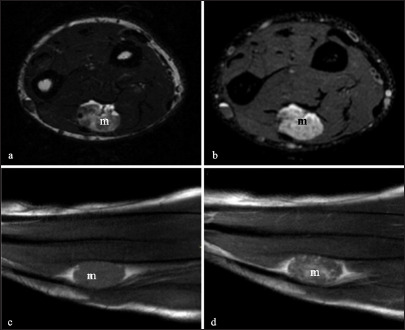

背景:动静脉畸形血管瘤(AVMH)是一种罕见的良性血管病变,常位于头部和颈部,很少发生在四肢。早期症状通常是非特异性的,这使得与其他良性病变(如神经鞘瘤)的临床鉴别诊断尤其具有挑战性。病例描述:我们报告一例25岁男性前臂病变。最初,临床和影像学特征提示神经鞘瘤,因为它位于周围神经,没有明显的血管征象。病变通过手术切除。组织病理学检查显示与AVMH相符的特征,证实了诊断。结论:该病例强调了包括AVMH在内的软组织病变鉴别诊断的重要性,特别是当位于周围神经的过程中,并模仿其他良性肿瘤,如神经鞘瘤。

Background: Arteriovenous malformation hemangioma (AVMH) is a rare, benign vascular lesion, often located in the head and neck and less frequently in the limbs. Early symptoms are typically nonspecific, making the clinical differential diagnosis with other benign lesions, such as schwannomas, particularly challenging.

Case description: We report the case of a 25-year-old male presenting with a lesion in the forearm. Initially, the clinical and imaging features suggested a schwannoma, due to its location along a peripheral nerve and the absence of distinctive vascular signs. The lesion was surgically excised. Histopathological examination revealed features consistent with AVMH, confirming the diagnosis.